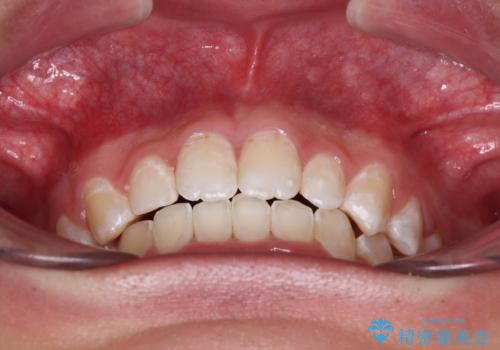

- 強い咬み合わせと前歯のデコボコを気にして来院された患者様です。

下顎前歯が全て隠れてしまうほどの深い咬合で、左右の奥歯は1歯対1歯で咬み合う状態でした。

前方に移動している上顎臼歯を補助装置にて遠心移動させることで1歯対2歯の臼歯咬合を目指し、同時に深い咬合を改善していくこととしました。